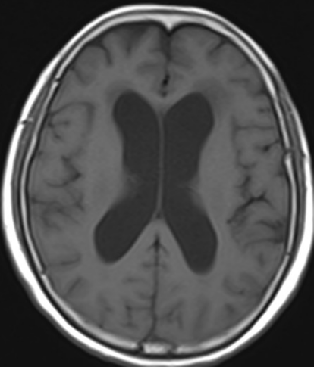

2014-10-17 CT

仍时有前额部疼痛,程度轻,调压190—200